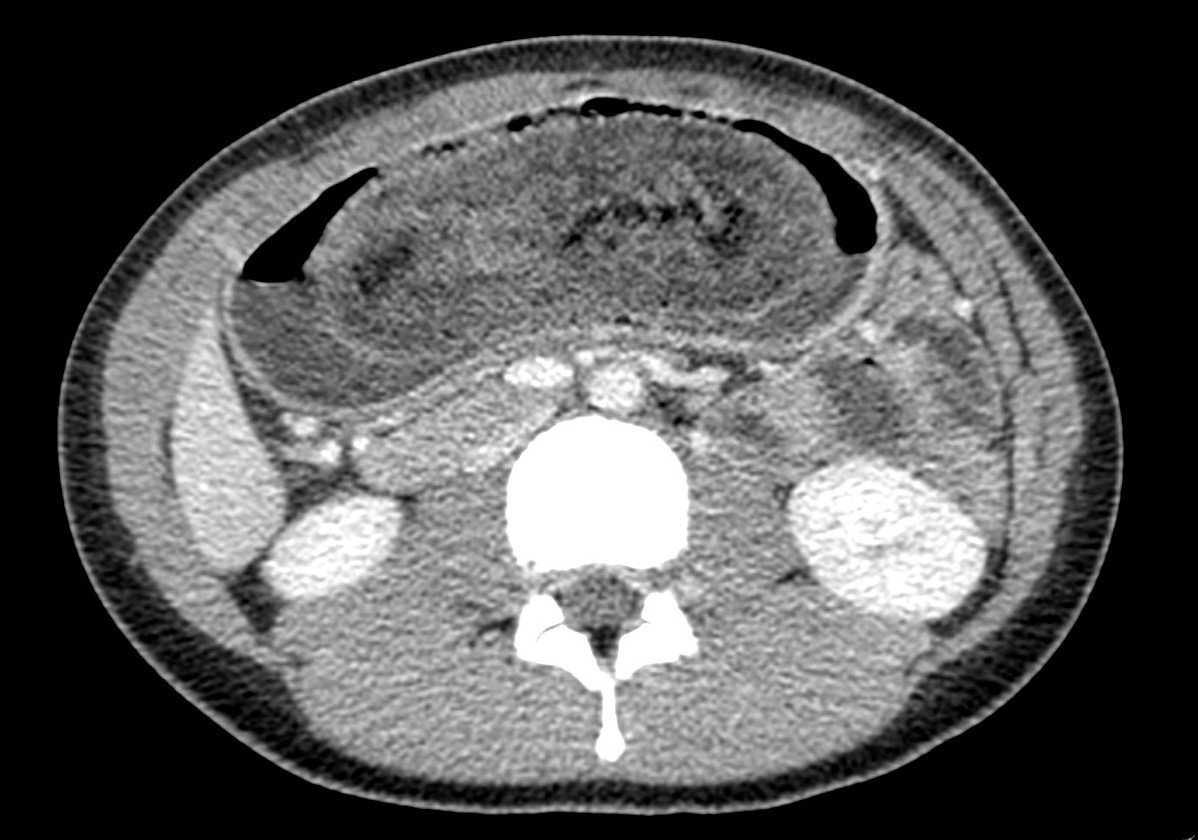

Finalmente, se realiza un TC abdominal:

Estamos ante un tricobezoar intrgástrico único. No hay obstrucción de asas intestinales.

- CT abdominal: Es la prueba de elección.

- Masa con baja densidad intraluminal + patrón de burbujas de aire moteado ( patrón característico).

- Edema de pared y engrosamiento de mucosa.

- El CT puede ayudar a distinguir entre un bezoar y particulas de comida. Los bezoares son redondos u ovoides, flotan en la superficie de agua/aire rodeados del contenido gástrico y que además muestran menor densidad que las partículas de comida. Los bezoares grandes tienden a rellenar todo el lumen y muestran burbujas distribuidas en el intersticio de la masa. Sin embargo, en ocasiones puede ser dificil difrenciar un bezoar de un cantidad considerable de comida retenida o de las heces si se localizan en el colon. Un hallazgo que puede ayudarnos, es identificar que dicha masa esta produciendo una obstrucción.

- La ventana estándar abdominal de (level, 40 H; width, 350 H) puede hacer muy dificil el diagnóstico de bezoar. Es recomendable bajar el Nivel/Level de la ventana hasta los L -1oo H o jugar con dichos niveles hasta identificar mejor las características del bezoar.